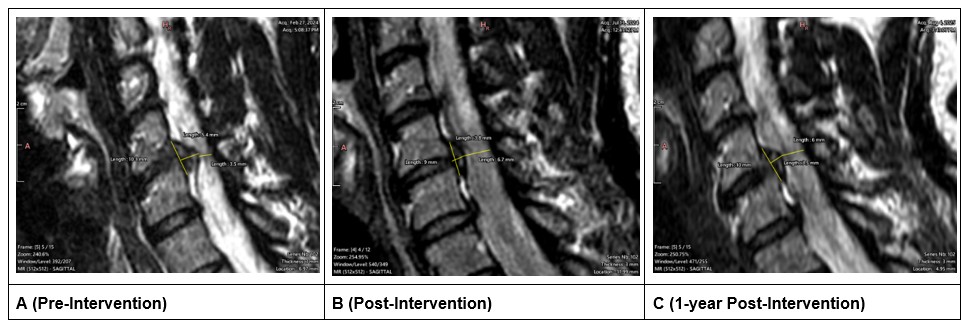

All MRI imaging obtained was assessed with Weasis DICOM Viewer (v4.6.6) and was assessed longitudinally (Figure 2) [14]. Following non-surgical spinal decompression treatment of the cervical spine, the anterior-posterior (AP) length of the lesion at C5–C6 decreased (Figures 3A and 3B) from 5.45 mm to 3.78 mm (-1.67 mm; 31% decrease) and the superior-inferior (SI) length of the lesion decreased from 10.27 mm to 9.00 mm (-1.27mm; 12% decrease; Figures 3A and 3B). After 1-year follow up, the AP length decreased by an additional 0.25 mm resulting in a total decrease of 1.92 mm (35% decrease); the SI length increased by 1.03mm at the 1-year follow-up resulting in an overall reduction of 0.24mm (10% decrease; Figures 3A and 3C).

Figure 3. Para-sagittal slice of the left-sided disc lesion. The lesion present on the left side across all three time points. A (pre-treatment), B (post-treatment), C (1 year follow-up).